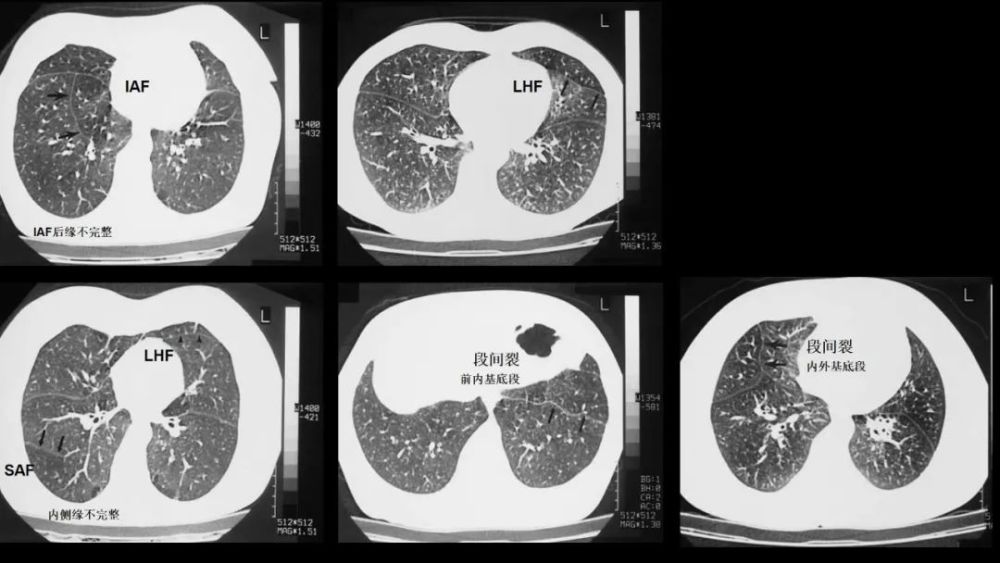

在解剖学上 , 肺叶间附属裂是肺叶间裂经常出现的变异 , 是脏层胸膜形成的除了常见的肺叶间裂以外的不同深度的裂隙 。 肺叶间附属裂是额外的 , 其支气管肺段及支气管动脉的排列都是正常的 , 是个别肺叶在发育过程中和邻近组织分离独立的一种现象 。 它可以是完全的 , 也可以是不全的 , 呈不同深度延伸至肺门 。 被附属裂分离的肺叶称为附属叶 。 研究的资料表明 , 附属裂大部分是不全的 , 从而导致附属叶与主叶之间存在或多或少的融合 。 在X线片上表现为细白线 , 除了位置的不同 , 类似于斜裂和水平裂 。 肺叶间附属裂经常在肺的解剖标本中被发现 , 在x线片和普通的CT扫描中经常被忽视或者误判 。 随着MSCT在临床的广泛应用 , MPR技术有利于观察肺叶间附属裂的分布情况和出现的频率 , 可为胸外科医师术前制定手术方案提供参考 。

Inferior accessory fissure

Twining’s line , 分隔下叶的内侧基底段

CT上的检出率:12% , 前位胸片显示率:5~8%R:L=5:1;多为不完整的 , 0.5~2cm